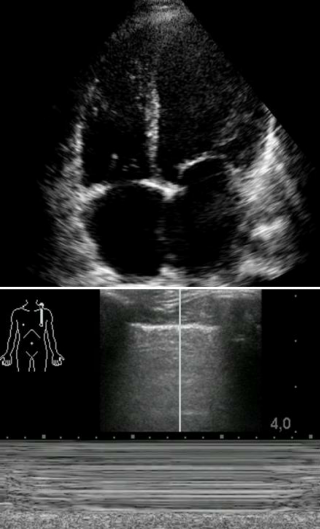

9:15 Grundlagen der transthorakalen Echokardiographie, Standardschnittebenen nach FoCUS, Was ist ein optimales Bild?

13:15 Abschätzung LV und RV Funktion

14:00 Orientierende Untersuchung von Klappenpathologien

14:30 Perikarderguss, Tamponade, Pleuraerguss, Thromben

15:00 Hämodynamische Instabilität und Reanimation